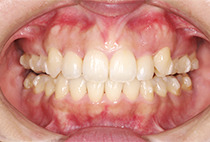

出っ歯と前歯のガタつきにお悩みだった20代女性の症例です。

また、気になっていたオトガイ(顎先)の左右差に対して、

を行い、フェイスラインも自然に整えました。

矯正は「歯並びを治す」だけではありません。

当院では、呼吸・噛み合わせ・顔貌バランス・美容までトータルに整える顎顔面治療を行っています。